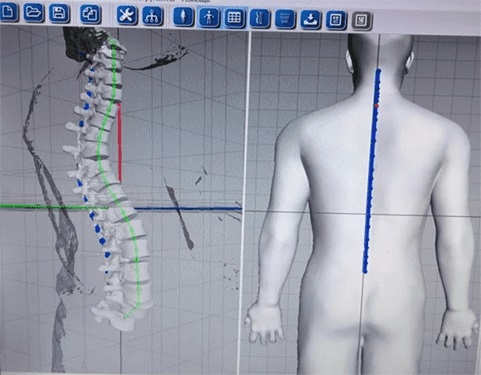

Оптическая диагностика позвоночника Diers: изображения и технологии

Раздел: Мир в картинках